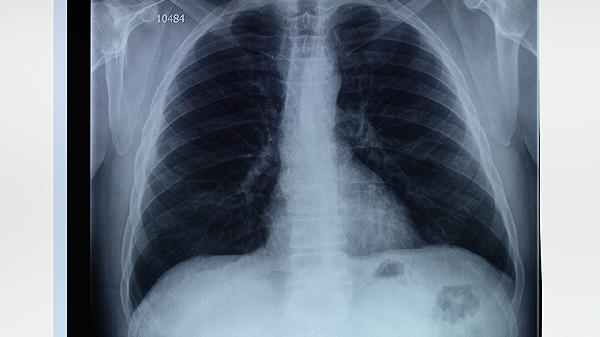

肺氣腫和小肺大泡的嚴(yán)重程度取決于病變的范圍和患者的身體狀況。肺氣腫和小肺大泡的嚴(yán)重性主要與病變范圍、肺功能受損程度、并發(fā)癥風(fēng)險(xiǎn)、癥狀表現(xiàn)及生活質(zhì)量影響等因素有關(guān)。

肺氣腫和小肺大泡的嚴(yán)重性與病變范圍密切相關(guān)。病變范圍越大,肺組織受損越嚴(yán)重,肺功能下降越明顯。局限性病變可能對(duì)整體肺功能影響較小,而彌漫性病變則可能導(dǎo)致嚴(yán)重的呼吸功能障礙。

肺氣腫和小肺大泡會(huì)導(dǎo)致肺功能下降,表現(xiàn)為肺活量減少、殘氣量增加、氣道阻力增大等。肺功能受損程度越嚴(yán)重,患者的呼吸困難和缺氧癥狀越明顯,嚴(yán)重時(shí)可能導(dǎo)致呼吸衰竭。

肺氣腫和小肺大泡可能引發(fā)多種并發(fā)癥,如自發(fā)性氣胸、肺部感染、肺動(dòng)脈高壓等。并發(fā)癥的發(fā)生會(huì)進(jìn)一步加重病情,增加治療難度,甚至危及生命。

肺氣腫和小肺大泡的嚴(yán)重性可以通過(guò)癥狀表現(xiàn)來(lái)評(píng)估。輕度患者可能僅在劇烈活動(dòng)時(shí)出現(xiàn)呼吸困難,而重度患者即使在靜息狀態(tài)下也會(huì)感到氣短,并伴有咳嗽、咳痰、乏力等癥狀。

肺氣腫和小肺大泡對(duì)患者的生活質(zhì)量有顯著影響。嚴(yán)重患者可能因呼吸困難而限制日?;顒?dòng),影響工作、社交和睡眠,甚至導(dǎo)致心理問(wèn)題如焦慮和抑郁。